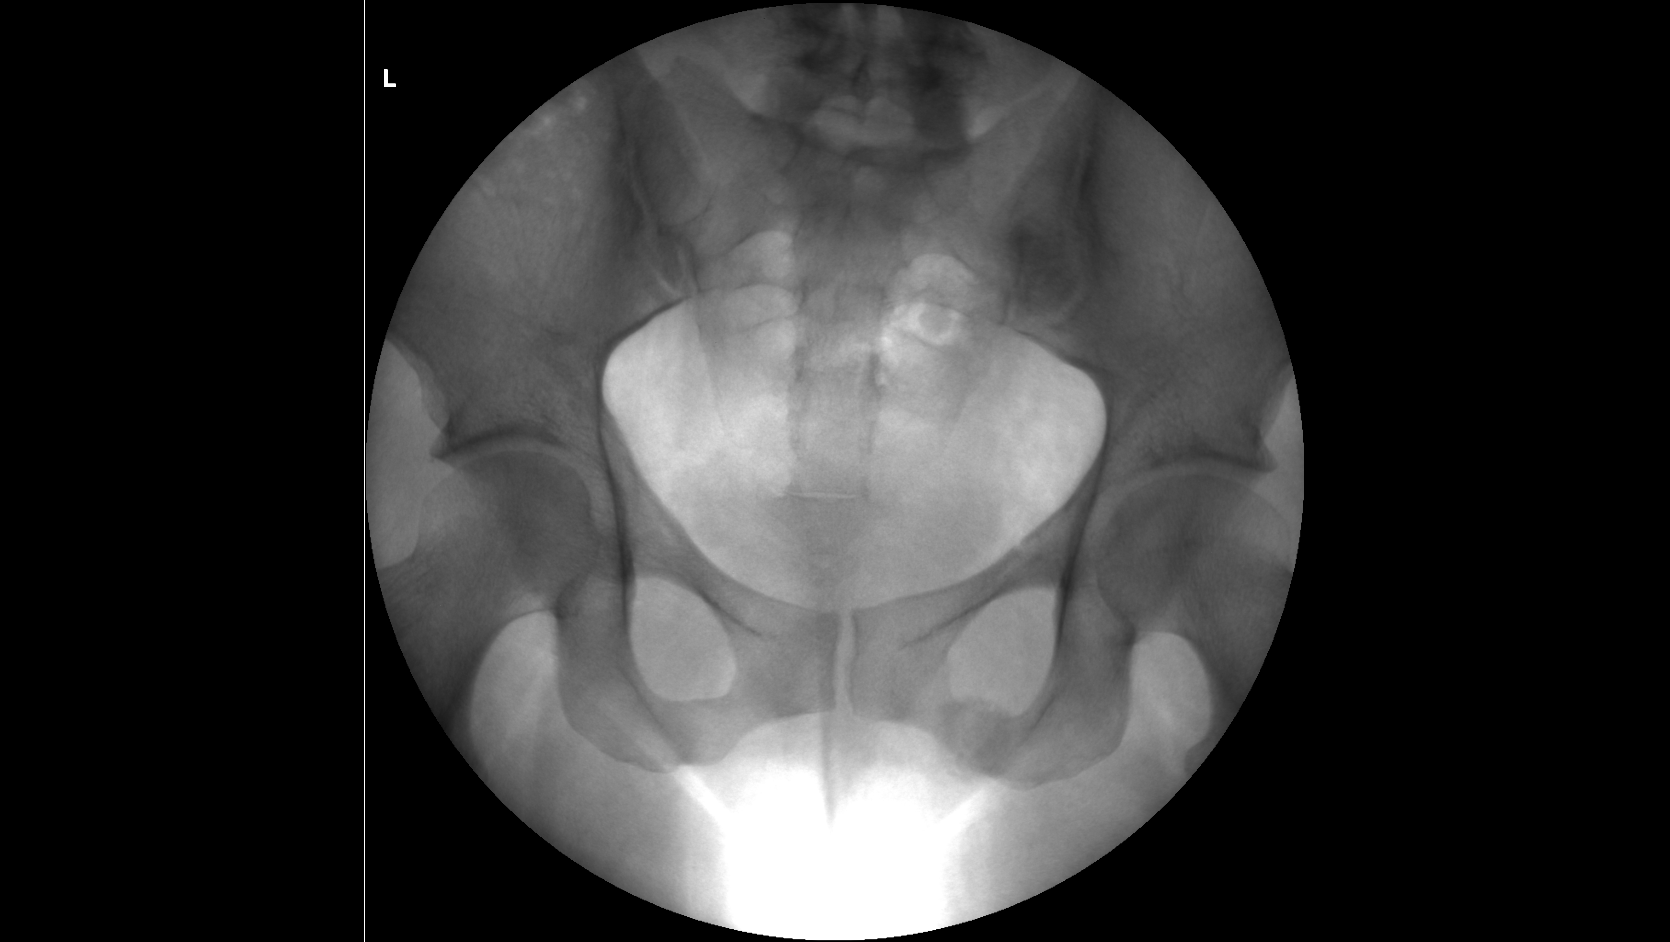

По вашей рекомендации я написал ходатайство о проведении повторной комиссионной экспертизы и сам в ней участвовал, так как разобрался с вашей помощью во всех деталях, практический, все включая следователя были уверены, что вред квалифицируют, как средней тяжести, но по результатам повторной экспертизы, каким то странным образом эксперты нашли еще один третий перелом правой лобковой кости, в результате чего вред здоровью стал действительно Тяжким.

Посмотрите, пожалуйста, третье заключение экспертизы, а то закрадывается сомнения о том, что смотрели три рентгенолага и установили три разных диагноза, и правильно ли они определили третий перелом.

Отправляю заключение комиссионной экспертизы и рентгенные снимки сразу после происшествия и по истечению двух месяце.

снимки сразу после аварии, через 2 месяца и через 3 месяца

На рентгенограммах хорошо видны переломы: правой лонной и правой седалищной костей, левой лонной кости. Перелома левой седалищной кости нет. "Условная граница" левой лонной и левой седалищной костей, на самом деле, находится на некотором расстоянии от места перелома левой лонной кости. Т.е. ссылка экспертов на прохождение линии перелома по этой условной границе представляется изрядно притянутой и, в любом случае, это непосредственно не свидетельствует о наличии перелома левой седалищной кости. Для оценки этой травмы как тяжкий вред нужен перелом типа "бабочки" всех четырех костей: правой лонной (он есть), правой седалищной (есть), левой лонной (есть), левой седалищной (нет!).

Убежден, что за такой перелом тяжкий вред давать неправильно. Это - вред здоровью средней тяжести (по п.7.1 вышеуказанного документа).

Путаница в сторонах переломов: на одном снимке противоположная сторона переломов верхней ветви лонной и ветви седалищной кости обозначена R, на остальных - L. Это может быть принципиальным. В остальном согласен: 6.1.23. отсутствует.